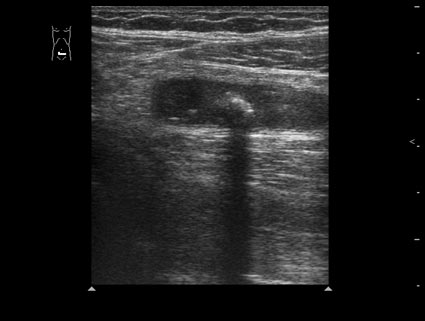

Острый флегмонозный аппендицит

Пациент 32 лет.

В правой подвздошной области определяется утолщенный аппендикс, не компрессируется при надавливании датчиком, в просвете определяется аппендиколит; окружающие аппендикс ткани инфильтрированы.